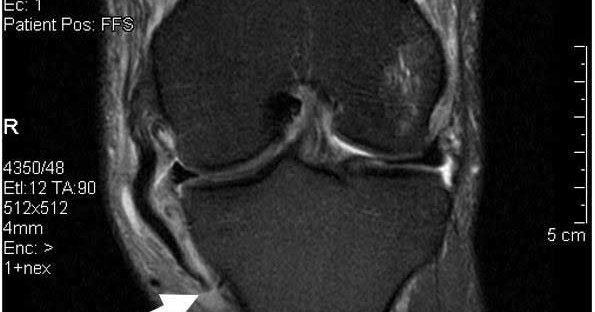

A medial #meniscustear may require surgery if it causes pain during twisting, turning, pivoting, or squatting...or if it’s a complex tear that risks further damage. Repairs can help prevent future arthritis in younger patients with healthy cartilage.

A medial meniscus tear is more common than a lateral meniscus tear, because it is firmly attached to the deep medial collateral ligament and the joint capsule.